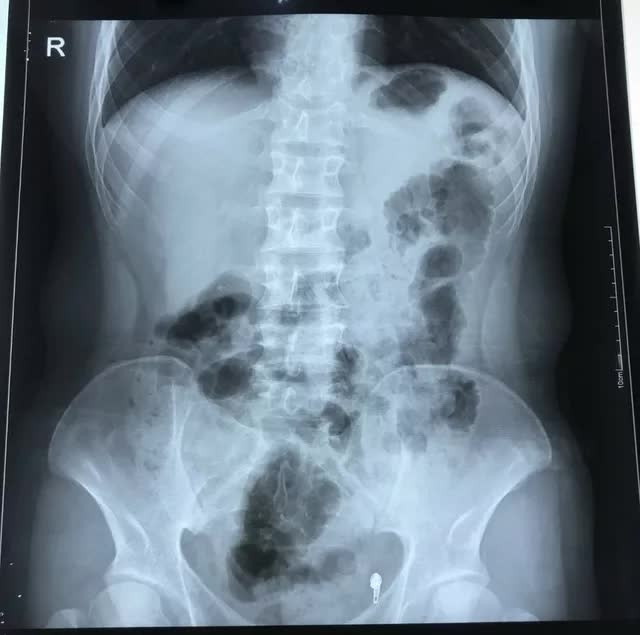

Theo kết quả siêu âm, chụp Xquang, bác sĩ chẩn đoán bệnh nhân viêm ruột thừa. Đặc biệt, phủ tạng chàng trai 17 tuổi đảo ngược, tim nằm bên phải. Ngay lập tức H. được đưa đi phẫu thuật. Chỉ sau khoảng 30 phút, ca phẫu thuật nội soi thành công, toàn bộ phần ruột thừa của bệnh nhân H. đã được cắt bỏ. Hiện tại, sức khỏe của bệnh nhân đã ổn định.

Điều đáng nói, các bác sĩ phát hiện trái tim của nam bệnh nhân nằm bên lồng ngực phải, ở vị trí đảo ngược so với người bình thường. Gia đình cho biết, trái tim và các tạng trong cơ thể của H, đều nằm ở vị trí đối lập so với mọi người. Ngoài ra, H, còn bị dị tật dính đầu chi, lỗ tiểu thấp. Mọi sinh hoạt hàng ngày của H. đều do gia đình giúp đỡ.

Được biết, đảo ngược phủ tạng là tình trạng bẩm sinh trong đó các cơ quan nội tạng trong ngực, bung đảo ngược phản chiều theo mặt phẳn đứng dọc so với vị trí bình thường. Tình trạng đảo ngược phủ tạng có thể hoàn toàn hoặc chỉ một vài cơ quan đơn thuần.

Đây là dạng dị tật có tính di truyền gene lặn tương đối hiếm gặp, với tỉ lệ khoảng 1/10.000 dân, trong đó có khoảng 5-10% có dị tật tim bẩm sinh, còn lại có cuộc sống hoàn toàn bình thường, không ảnh hưởng đến sức khỏe người bệnh.